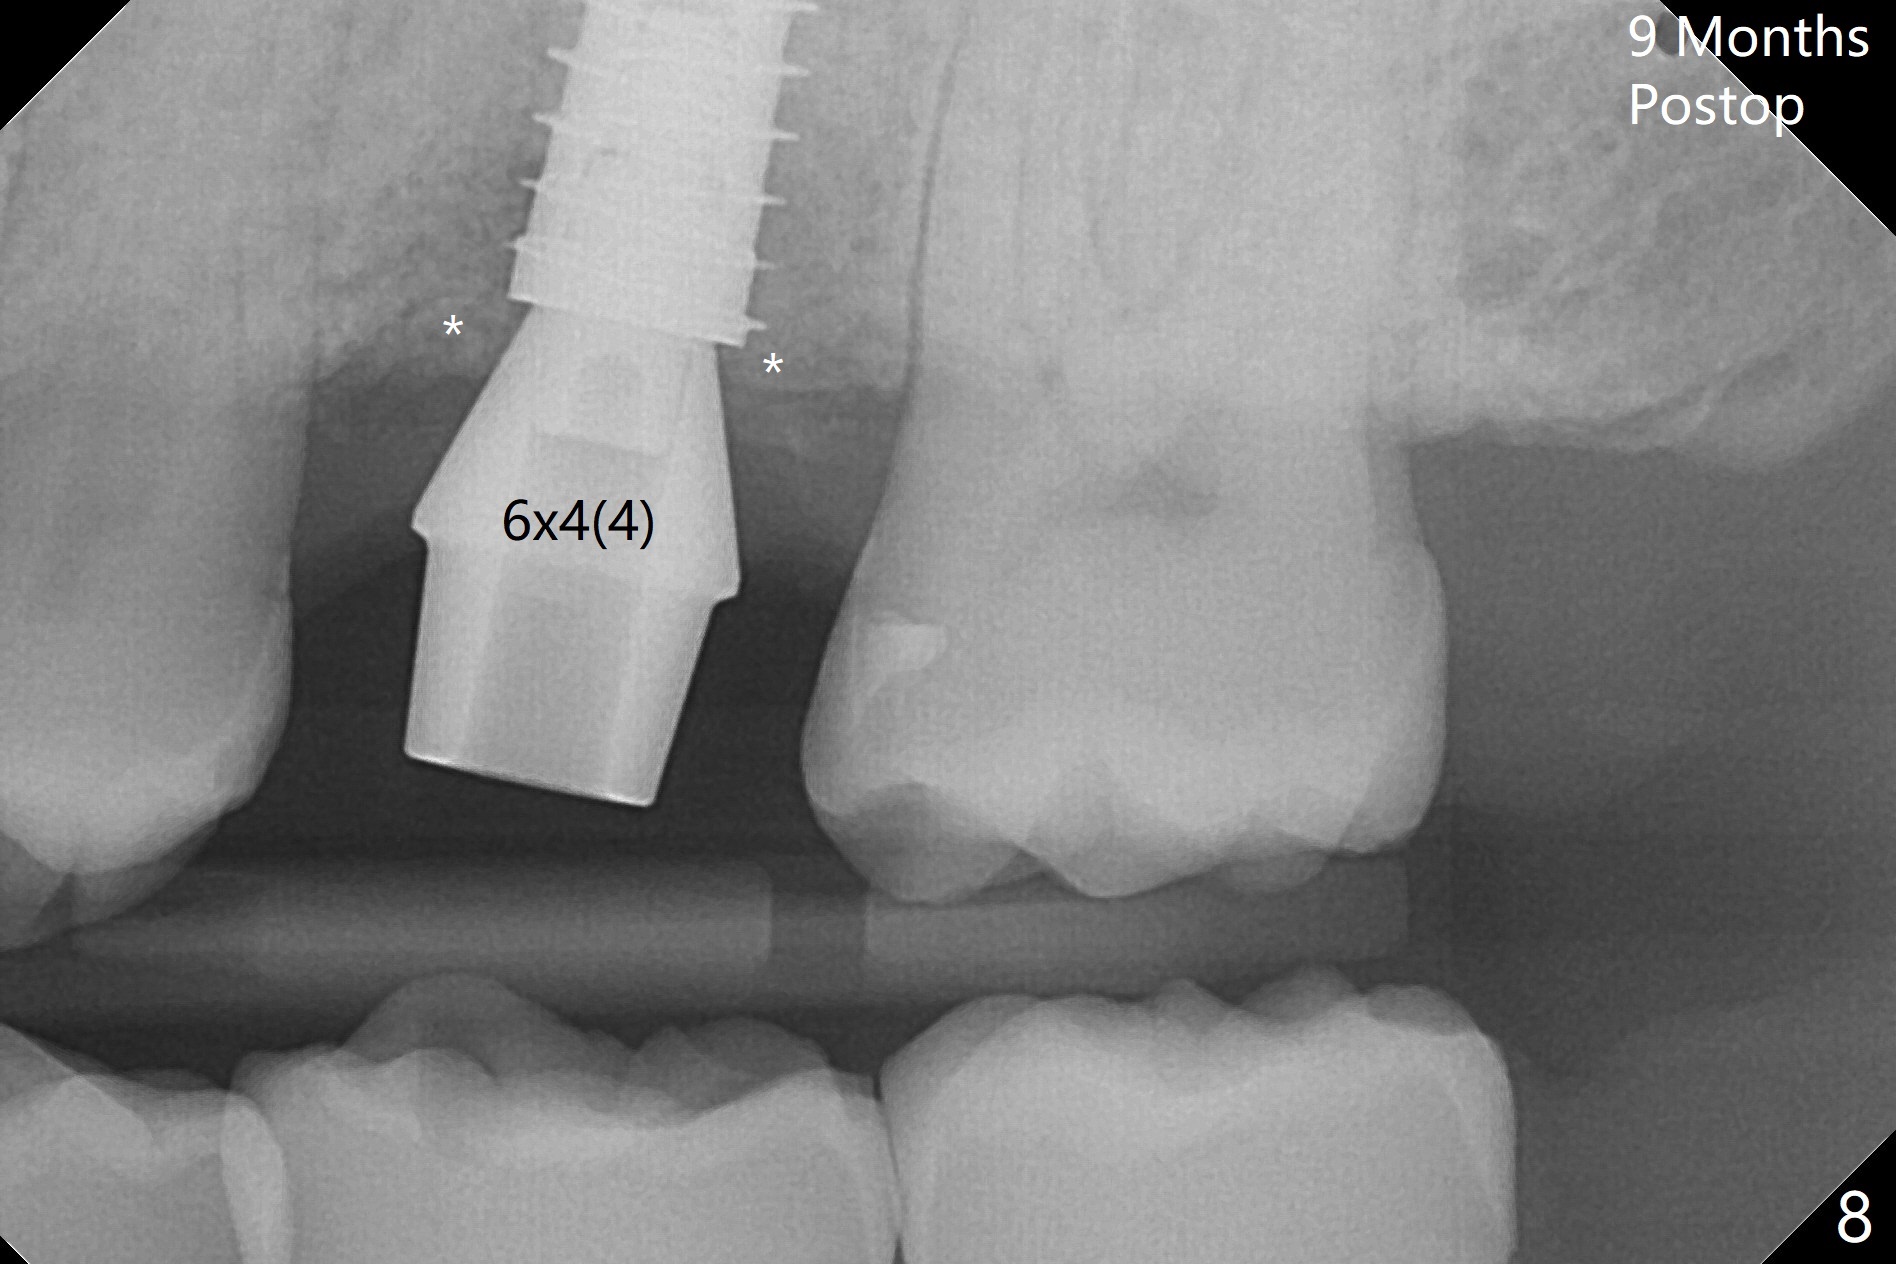

With modification of drill sequence in the last 3 steps (4.5x7.3, 4.0x8.5 and 3.5x10 mm drills) at #14 and sinus lift (Fig.1), a 5x9 mm implant is placed with ~ 50 Ncm following back up twice. Sticky bone mixed with autogenous bone (Fig.1,2 white *) is placed in the sockets before and after placement of a 6.5x5.7(2) mm abutment. Since the palatal gingival margin is recessive (Fig.3 ^), a palatal socket shield retains to prevent further recession (Fig.4 in the end of periodontal probe). Because the margin of the abutment is low, it changes to one with longer cuff (Fig.5). An immediate provisional is fabricated (Fig.6,7 P). The bone graft is indistinguishable from the original alveolus 9 months postop (Fig.8 *). The palatal socket shield is exposed 10 months postop (Fig.9 <). Since the implant is intentionally placed buccal; the sheath is not essential.